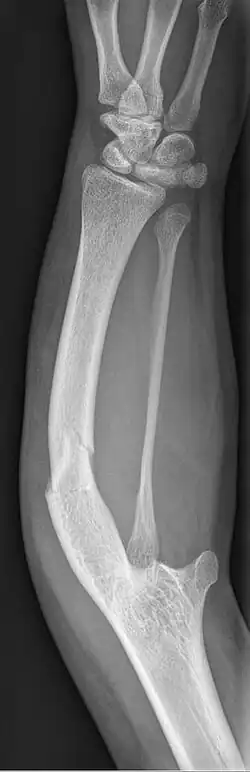

| Ulnar hypoplasia | |

| Symptoms | Missing or underdeveloped ulnae bone |

Ulnar dysplasia also known as ulnar longitudinal deficiency, ulnar club hand or ulnar aplasia/hypoplasia is a rare congenital malformation which consists of an underdeveloped or missing ulnae bone, causing an ulnar deviation of the entire wrist. The muscles and nerves in the hand may be missing or unbalanced. In severe cases, ulnar digits (e.g. ring and pinky finger) may be missing. Sometimes, radial dysplasia occurs alongside this malformation.[2] This condition occurs in 1 in 100,000 live births.[3][4][5][6] Sometimes, other orthopedic problems occur alongside this malformation, such as scoliosis.[7]

Type 1: The mildest type of ulnar dysplasia. The ulnae is slightly shorter than average and there is a barely noticeable wrist deviation

Type 2: The ulnae is moderately-severely smaller than normal. The radius is deviated and so is the hand

Type 3: The ulnae is completely missing. The radius is even more deviated, causing a severe ulnar deviation of the hand.

Type 4: The most severe type of ulnar dysplasia, the ulnae is completely missing, and the wrist is severely deviated. The elbow bones are fused together, so the elbow has reduced mobility